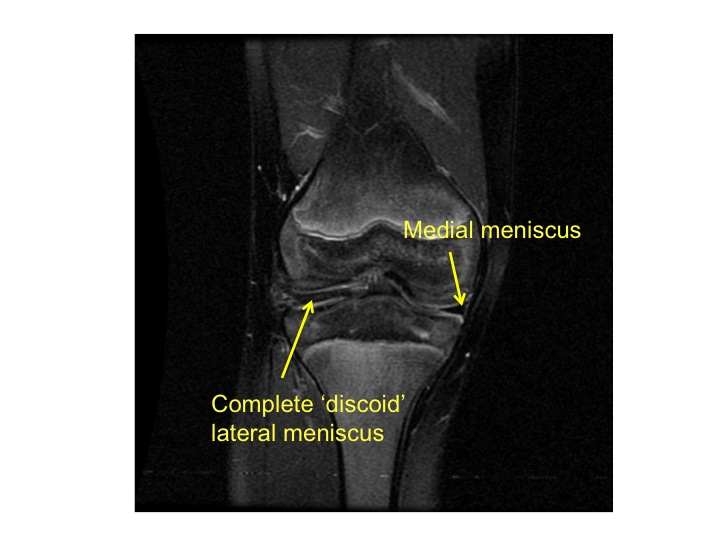

It is one of two menisci of the knee, the other being the medial meniscus.it is nearly circular and covers a larger portion of the articular surface than the medial. Medial, lateral and odd facet on the posterior surface of the patella articulate with the medial and lateral condyles of the femur. Posterior horn is wider than the anterior horn.

A meniscus tear is a common knee injury. The function of the menisci is to assist the movement of the bones over each other, to deepen the tibial plateau and to act as a form of shock absorption. The knee meniscus is a special layer of cartilage that lines the knee joint.

Researchers believe they may play a role in compressing synovial fluid in the knee joint, reducing friction and wear. The knee menisci are fibrocartilaginous structures that sit within the knee joint, deepening the tibiofemoral articulation. 14 hacks to eliminate inflammation naturally